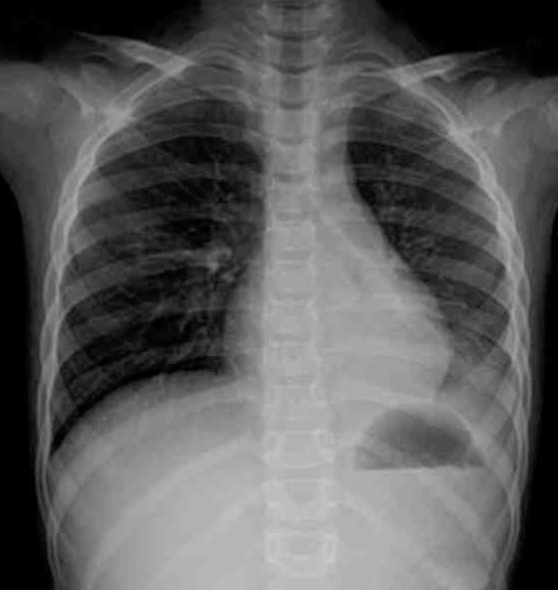

6세 여아가 5일 전부터 기침과 발열이 있어 병원에 왔다. 혈압 90/60 mmHg, 맥박 72회/분, 호흡 20회/분, 체온 37.3°C이다. 혈액검사 결과는 다음과 같다. 가슴 X선사진이다. 검사는?

CXR: LLLF haziness

• 흉부 X선에서 LLLF에서 관찰되는 mild opacity가 확인되므로 발열의 원인은 폐렴인 것으로 추정된다.